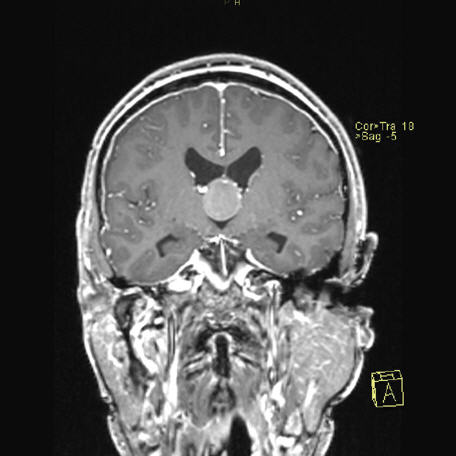

Veliko področje nevrologije predstavljajo bolezni živčevja, ki so v zadnjih 10 letih bistveno bolje zdravljive zaradi izjemnega razvoja zdravil številnih subspecialističnih nevroloških stanj. Med ta stanja spadajo: demence, epilepsija, Parkinsonova bolezen in multipla skleroza. Nevrofiziologi se posebej ukvarjajo z boleznimi, ki prizadenejo centralni živčni sistem in periferne živce, pa tudi bolezni mišic. Specifične nevrofiziološke preiskave omogočajo diagnostiko bolezni mišic, živčno-mišičnega stika, samega živca, hrbtenjače ali pa skorje možganov.